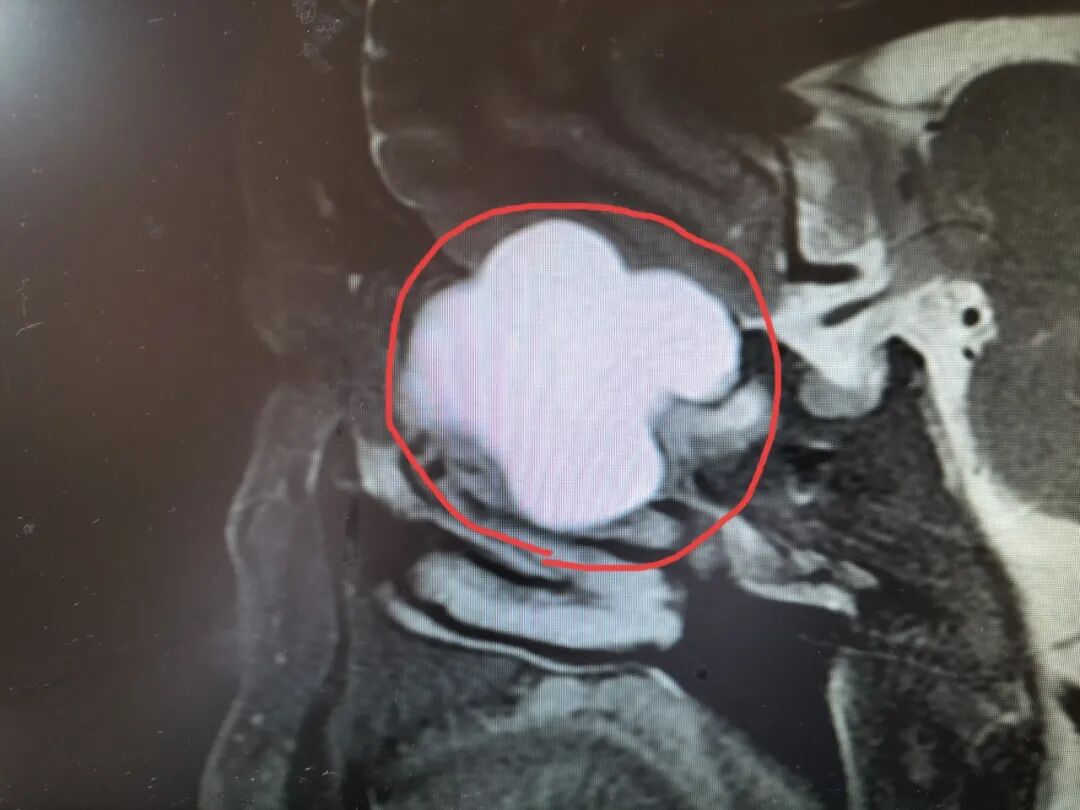

然而,细心的张俊杰医师发现马先生的左眼有轻微突出,怀疑问题可能不在眼睛本身。追问发现患者还有多年的鼻窦疾病,当即进行眼眶MRI检查。

真相浮出水面——筛窦内长了一个乒乓球大小的粘液囊肿,直接压迫视神经!